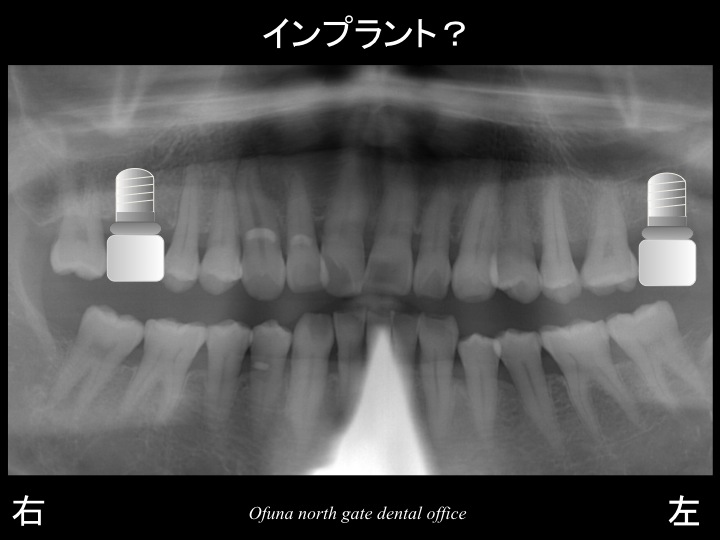

本日の症例の方は、上顎の左右奥歯が1歯づつ欠損している方です。

早速初診時のレントゲンを見てみましょう!

以下のレントゲンの●:赤丸が欠損部位です。